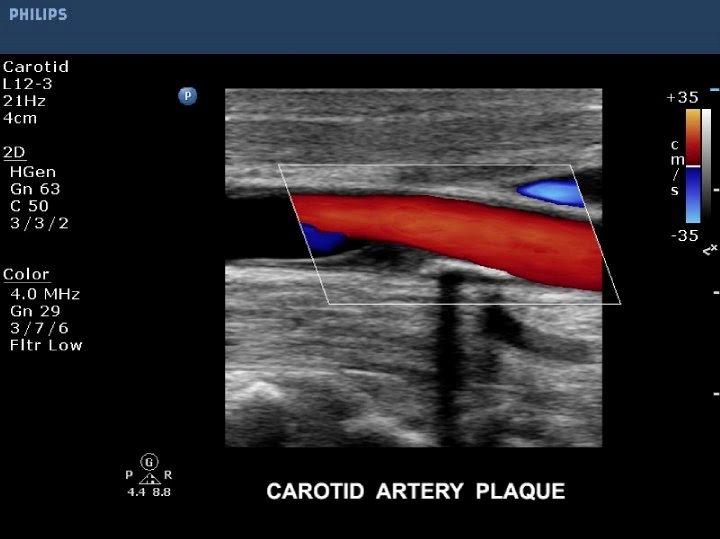

Varis hastalığında kan kaçağı (reflü) sonucu oluşan varislerin çoğu çıplak gözle görülebilir; bunlar buzdağının görünen kısmını oluştururlar. Ancak kapak yetmezliği sonucu varise neden olan damar ya da damarlar, yani olayın esas nedeni çıplak gözle görülemez ya da elle yapılan muayene ile anlaşılamaz. Buzdağının görünmeyen kısmını oluşturan bu damarlar ancak “renkli Doppler ultrasonografi” denen özel bir ultrason cihazıyla görülebilir.

Bu cihazla ayrıca cildin alt kısımlarında yer alan ve çıplak gözle görülemeyen varisler ile bacağın atardamar ve derin toplardamar sistemi de görüntülenebilir. Bu nedenle her varis hastası mutlaka önce renkli Doppler ultrasonografi ile incelenmeli, hastalıklı damarların bir “haritası” çıkarılmalı ve tedavi bu haritaya göre yapılmalıdır. Renkli Doppler ultrasonografi mutlaka deneyimli bir hekim (tercihan radyolog) tarafından yapılmalıdır, çünkü varis hastalığında yanlış ya da yetersiz tedavilerin en önemli nedeni renkli Doppler ultrasonografi tetkikinin yanlış yapılması ya da yorumlanmasıdır .

BOYUN KAROTİS VERTEBRAL ARTERLER RENKLİ DOPPLER